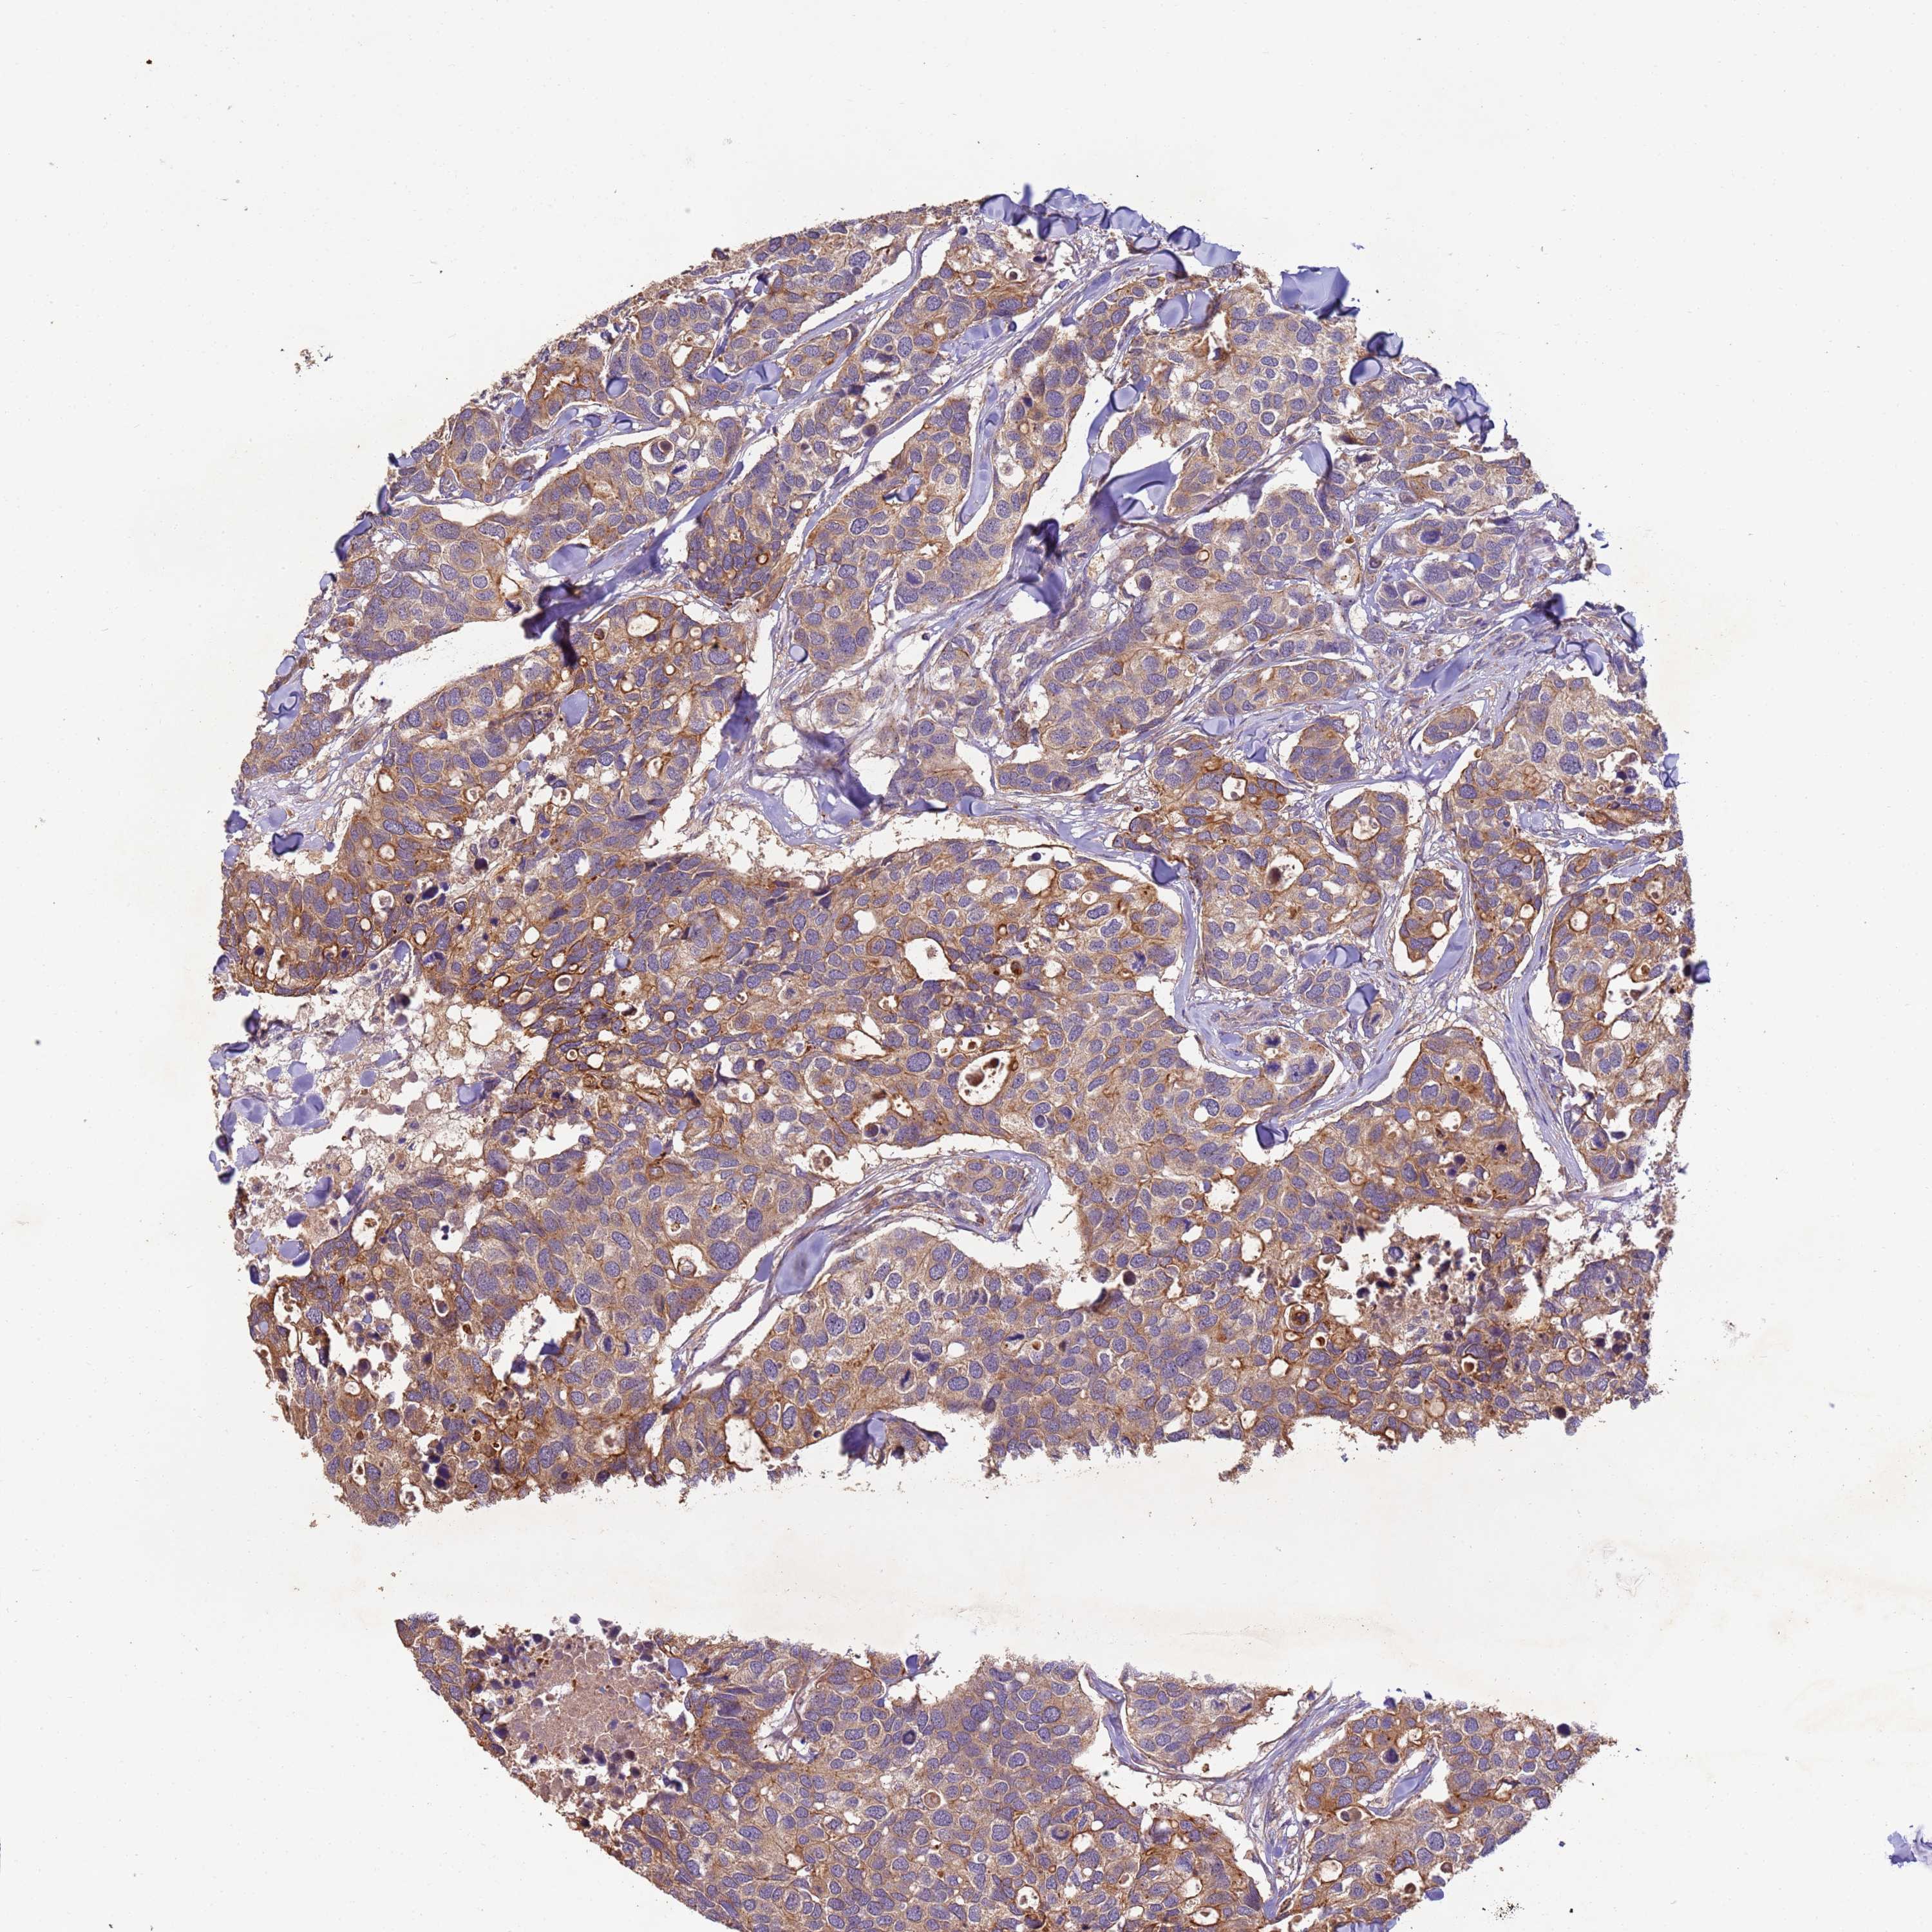

CANCER BREAST CANCER Show tissue menu

BRCA TCGA BRCA VALIDATION PROTEIN EXPRESSION